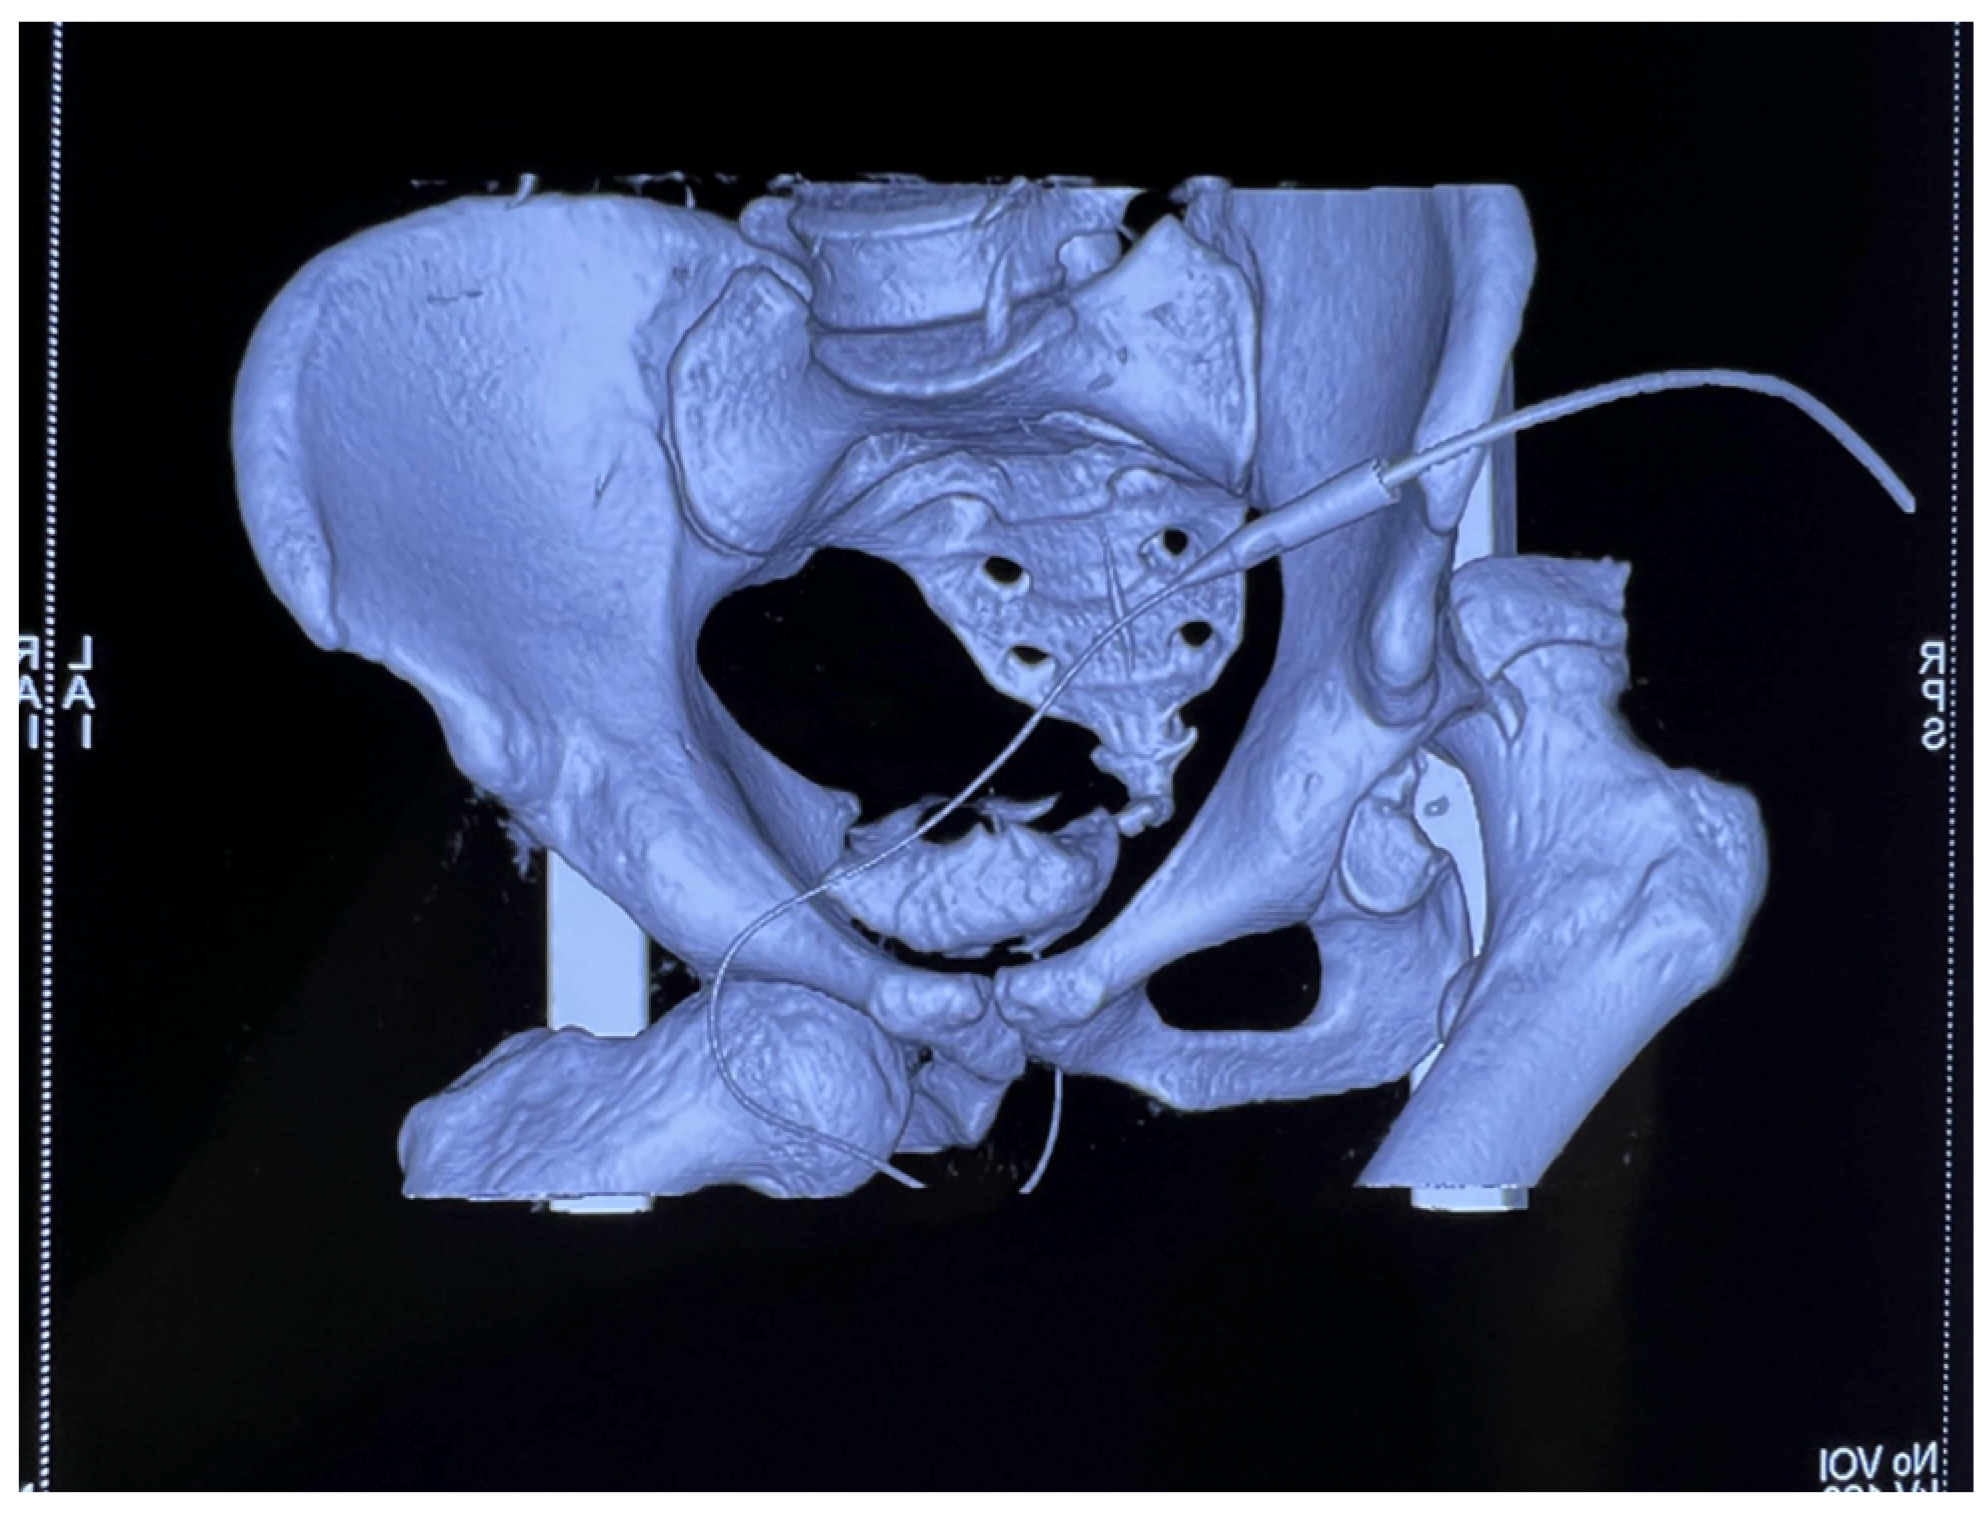

Anteroposterior (AP) pelvic radiographs immediately confirmed the presence of a bilateral asymmetric hip dislocation (Figure 1). The right femoral head was displaced posteriorly beyond the acetabular rim, with an associated acetabular posterior wall fracture, while the left femoral head was displaced anteroinferiorly into the obturator foramen, indicating an obturator-type anterior dislocation.

Figure 1. AP radiograph of the pelvis showing bilateral asymmetric hip dislocation with right femoral head displaced posteriorly beyond the acetabular rim, with an associated acetabular posterior wall fracture, while the left femoral head is displaced anteroinferiorly into the obturator foramen.